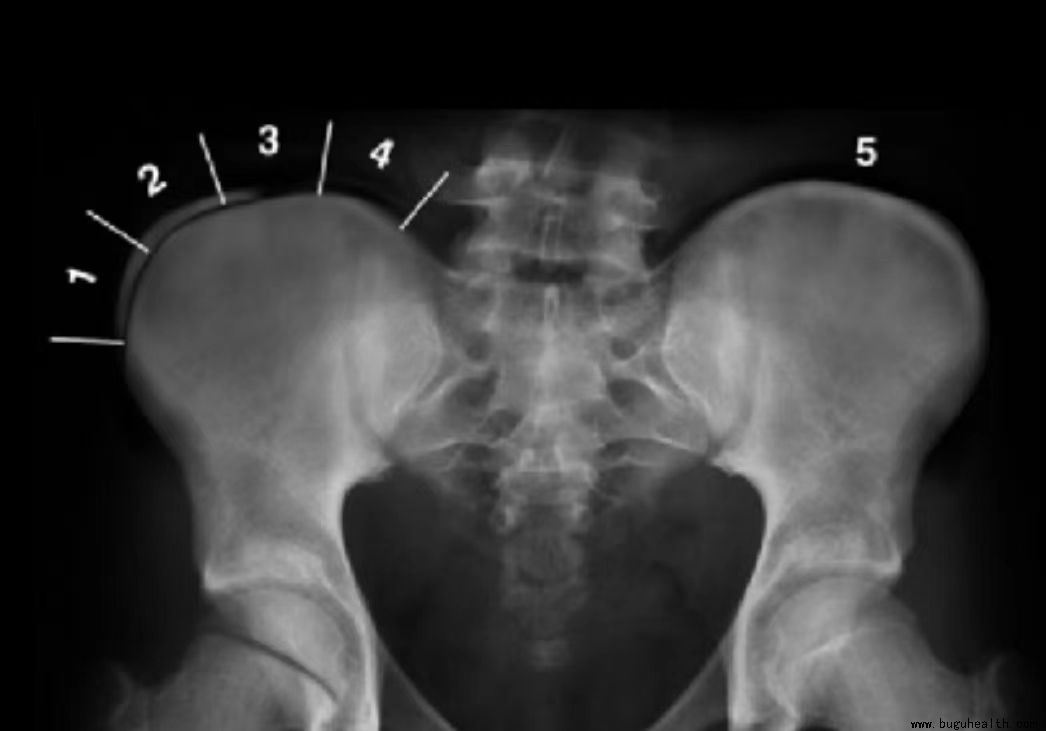

一、髂骨上方骨骺线闭合程度判断侧弯恶化风险: risser指数数越小,脊柱侧弯的恶化风险也就越大。

综合考虑:cobb角-3×骨龄(Risser指数)